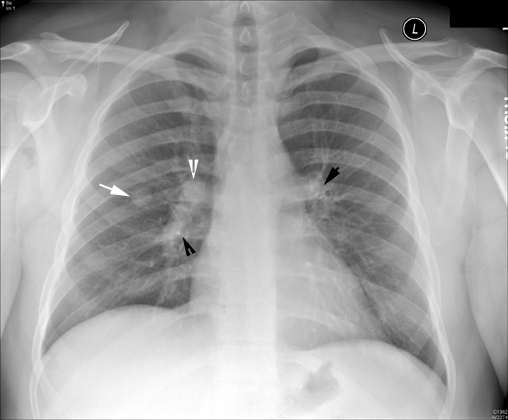

Solitary pulmonary nodulePET Scan: Increased isotope concentration corresponding to solitary pulmonary nodule consistent with malignancy. |

Solitary pulmonary nodule